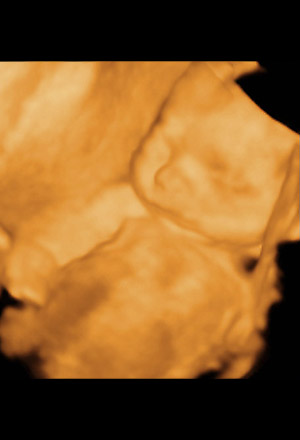

By 20 weeks, the top of the uterus is at the belly button. The baby weighs about 300 grams (10.6 ounces) and about 16 cm (6.5 inches) long, and is covered in a fine hair called lanugo. Fingerprints are developing as well as permanent teeth buds behind the baby teeth that are already formed. Gender is usually visible through ultrasound by now. The baby can suck a thumb, yawn, stretch, and make faces. You may be able to feel your baby move, which is called "quickening." Loud noises may even cause your baby to startle.